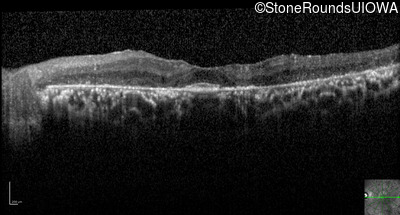

Optical Coherence Tomography - Left - 20/40 -1

Exemplar / OCT Stack

OCT Stack